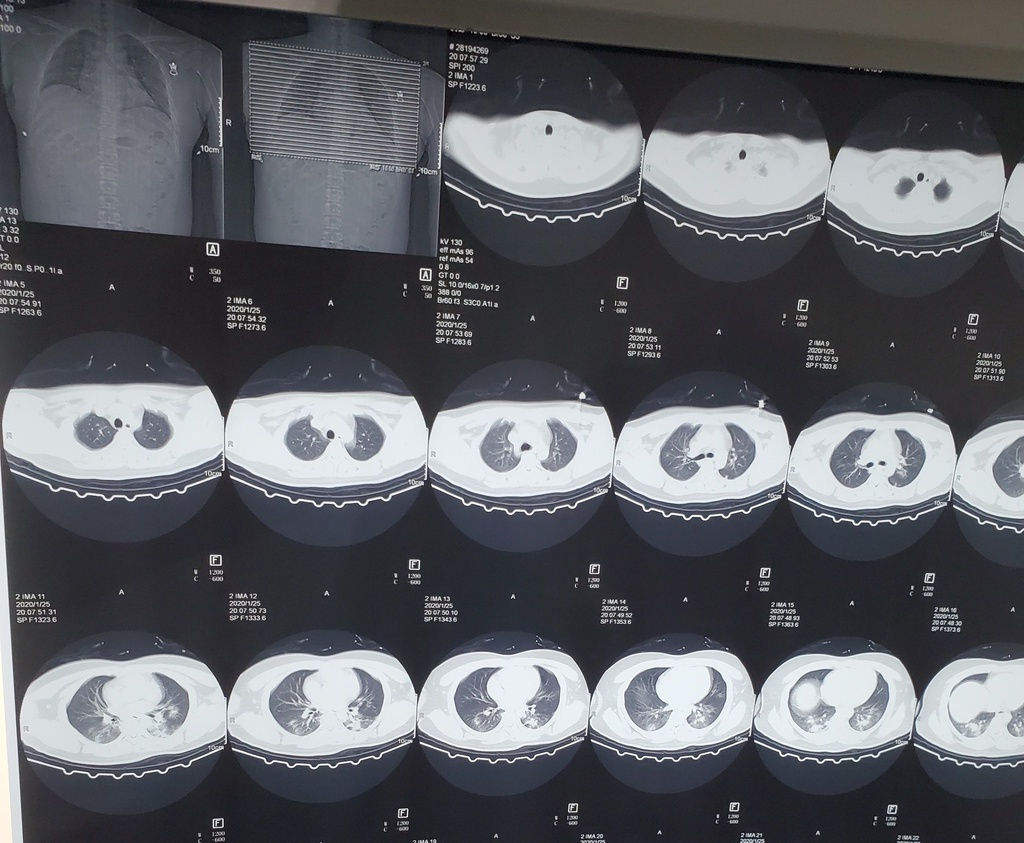

virus corona lan rong anh 3

Hình chụp CT hai lá phổi của một bệnh nhân nữ 33 tuổi ở Lan Châu, Trung Quốc. Trong hình A, có nhiều "đốm trắng" mờ như thủy tinh ở thùy phải và sau đỉnh thùy trái. Hình B là phổi chụp sau 3 ngày theo dõi bệnh nhân. Nó cho thấy những đốm trắng ngày càng lan rộng bên trong phổi người bệnh, "xâm chiếm" đỉnh sau thùy phải và sau đỉnh của thùy trái. Ảnh: RSNA.